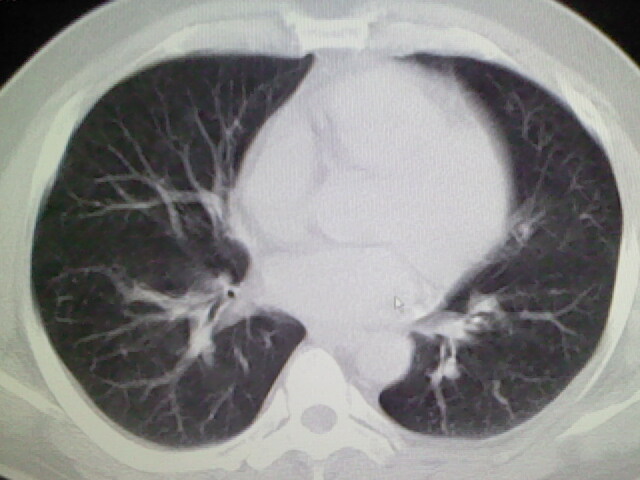

标题: CT17932:临床怀疑肺栓塞

男,34岁,自觉右侧胸痹,胸闷3天余

左上肺局限片状透光度增强区,肺纹理稀少,可考虑局限性肺气肿。

左上肺局限性肺透光度减低,肺纹理稀少;这虽然符合早期肺栓塞的改变,但与局限性肺气肿难以鉴别。

书上讲早期肺栓塞就是表现肺透光度减低,肺纹稀少。